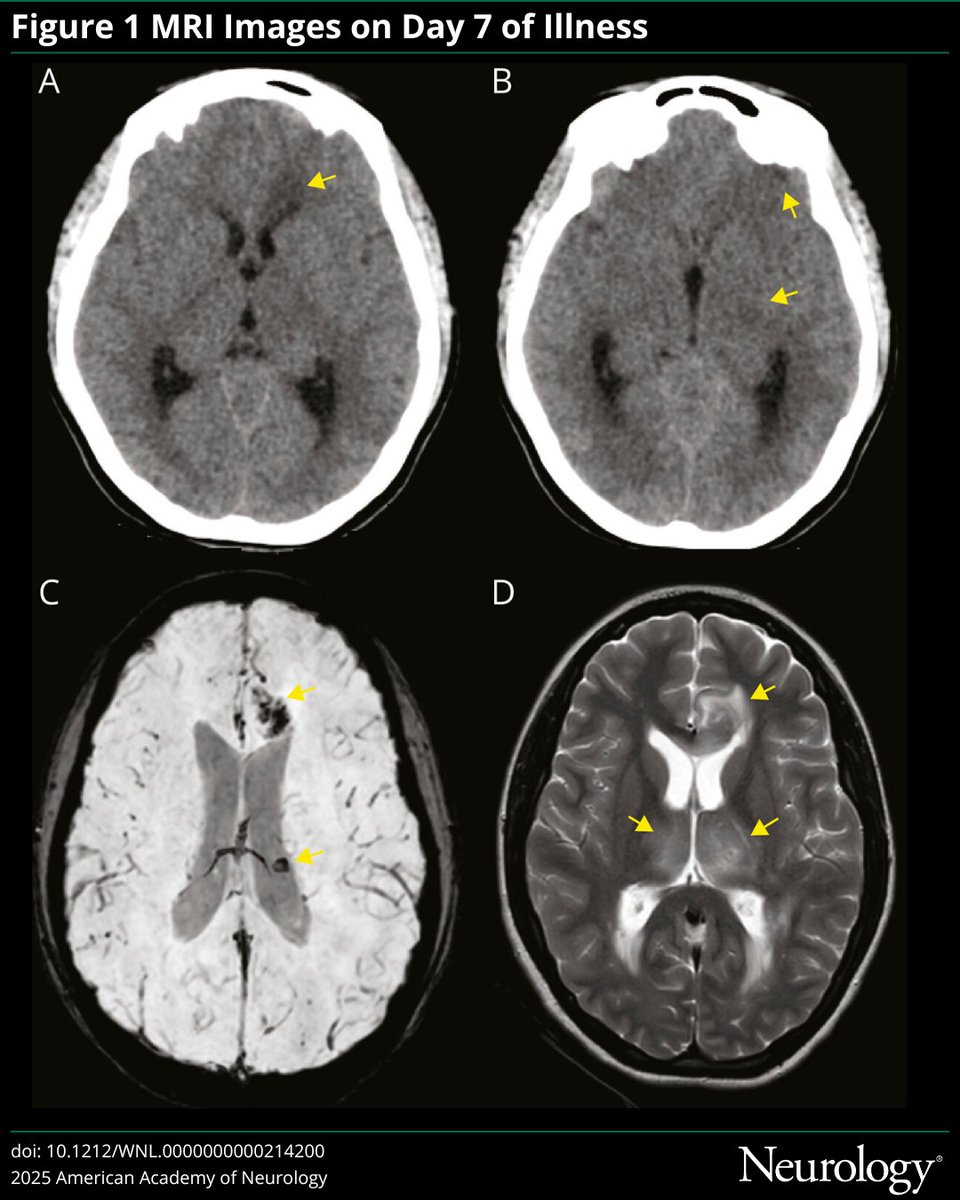

This #NeuroImage case highlights acute hemorrhagic necrotizing encephalitis as the initial radiologic manifestation of CNS tuberculosis: hubs.ly/Q03Mr25Z0